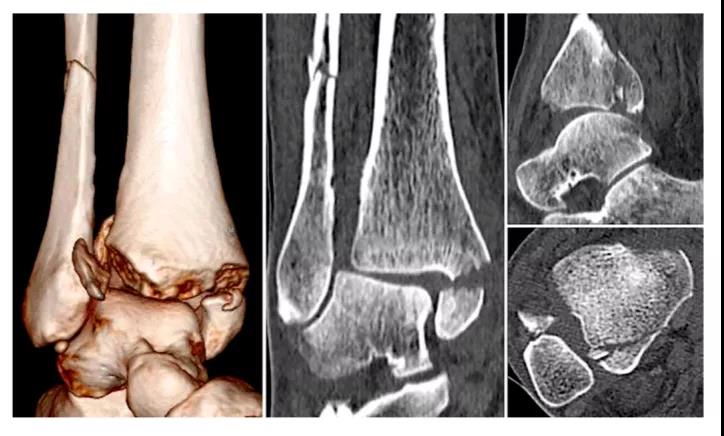

② 四踝骨折典型病例图。